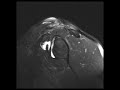

Type 2 SLAP Tear

36-year-old male with chronic left shoulder pain. The MR arthrogram images demonstrate a chondrolabral separation at the superior aspect of the left glenohumeral joint compatible with a type II SLAP tear. In addition, there is absence of the anterior superior labrum with hypertrophy of the middle glenohumeral ligament and prominence of the anterior band of the inferior glenohumeral ligament. Of the 10 different types of SLAP tears, type II reflect detachment of the superior labrum and biceps anchor from the underlying superior glenoid. In patients less than 40 years of age, these are usually associated with Bankart lesions. In older patients greater than 40 years of age, they are usually associated with rotator cuff tears. Treatment for a type II slap tear requires surgical reattachment.